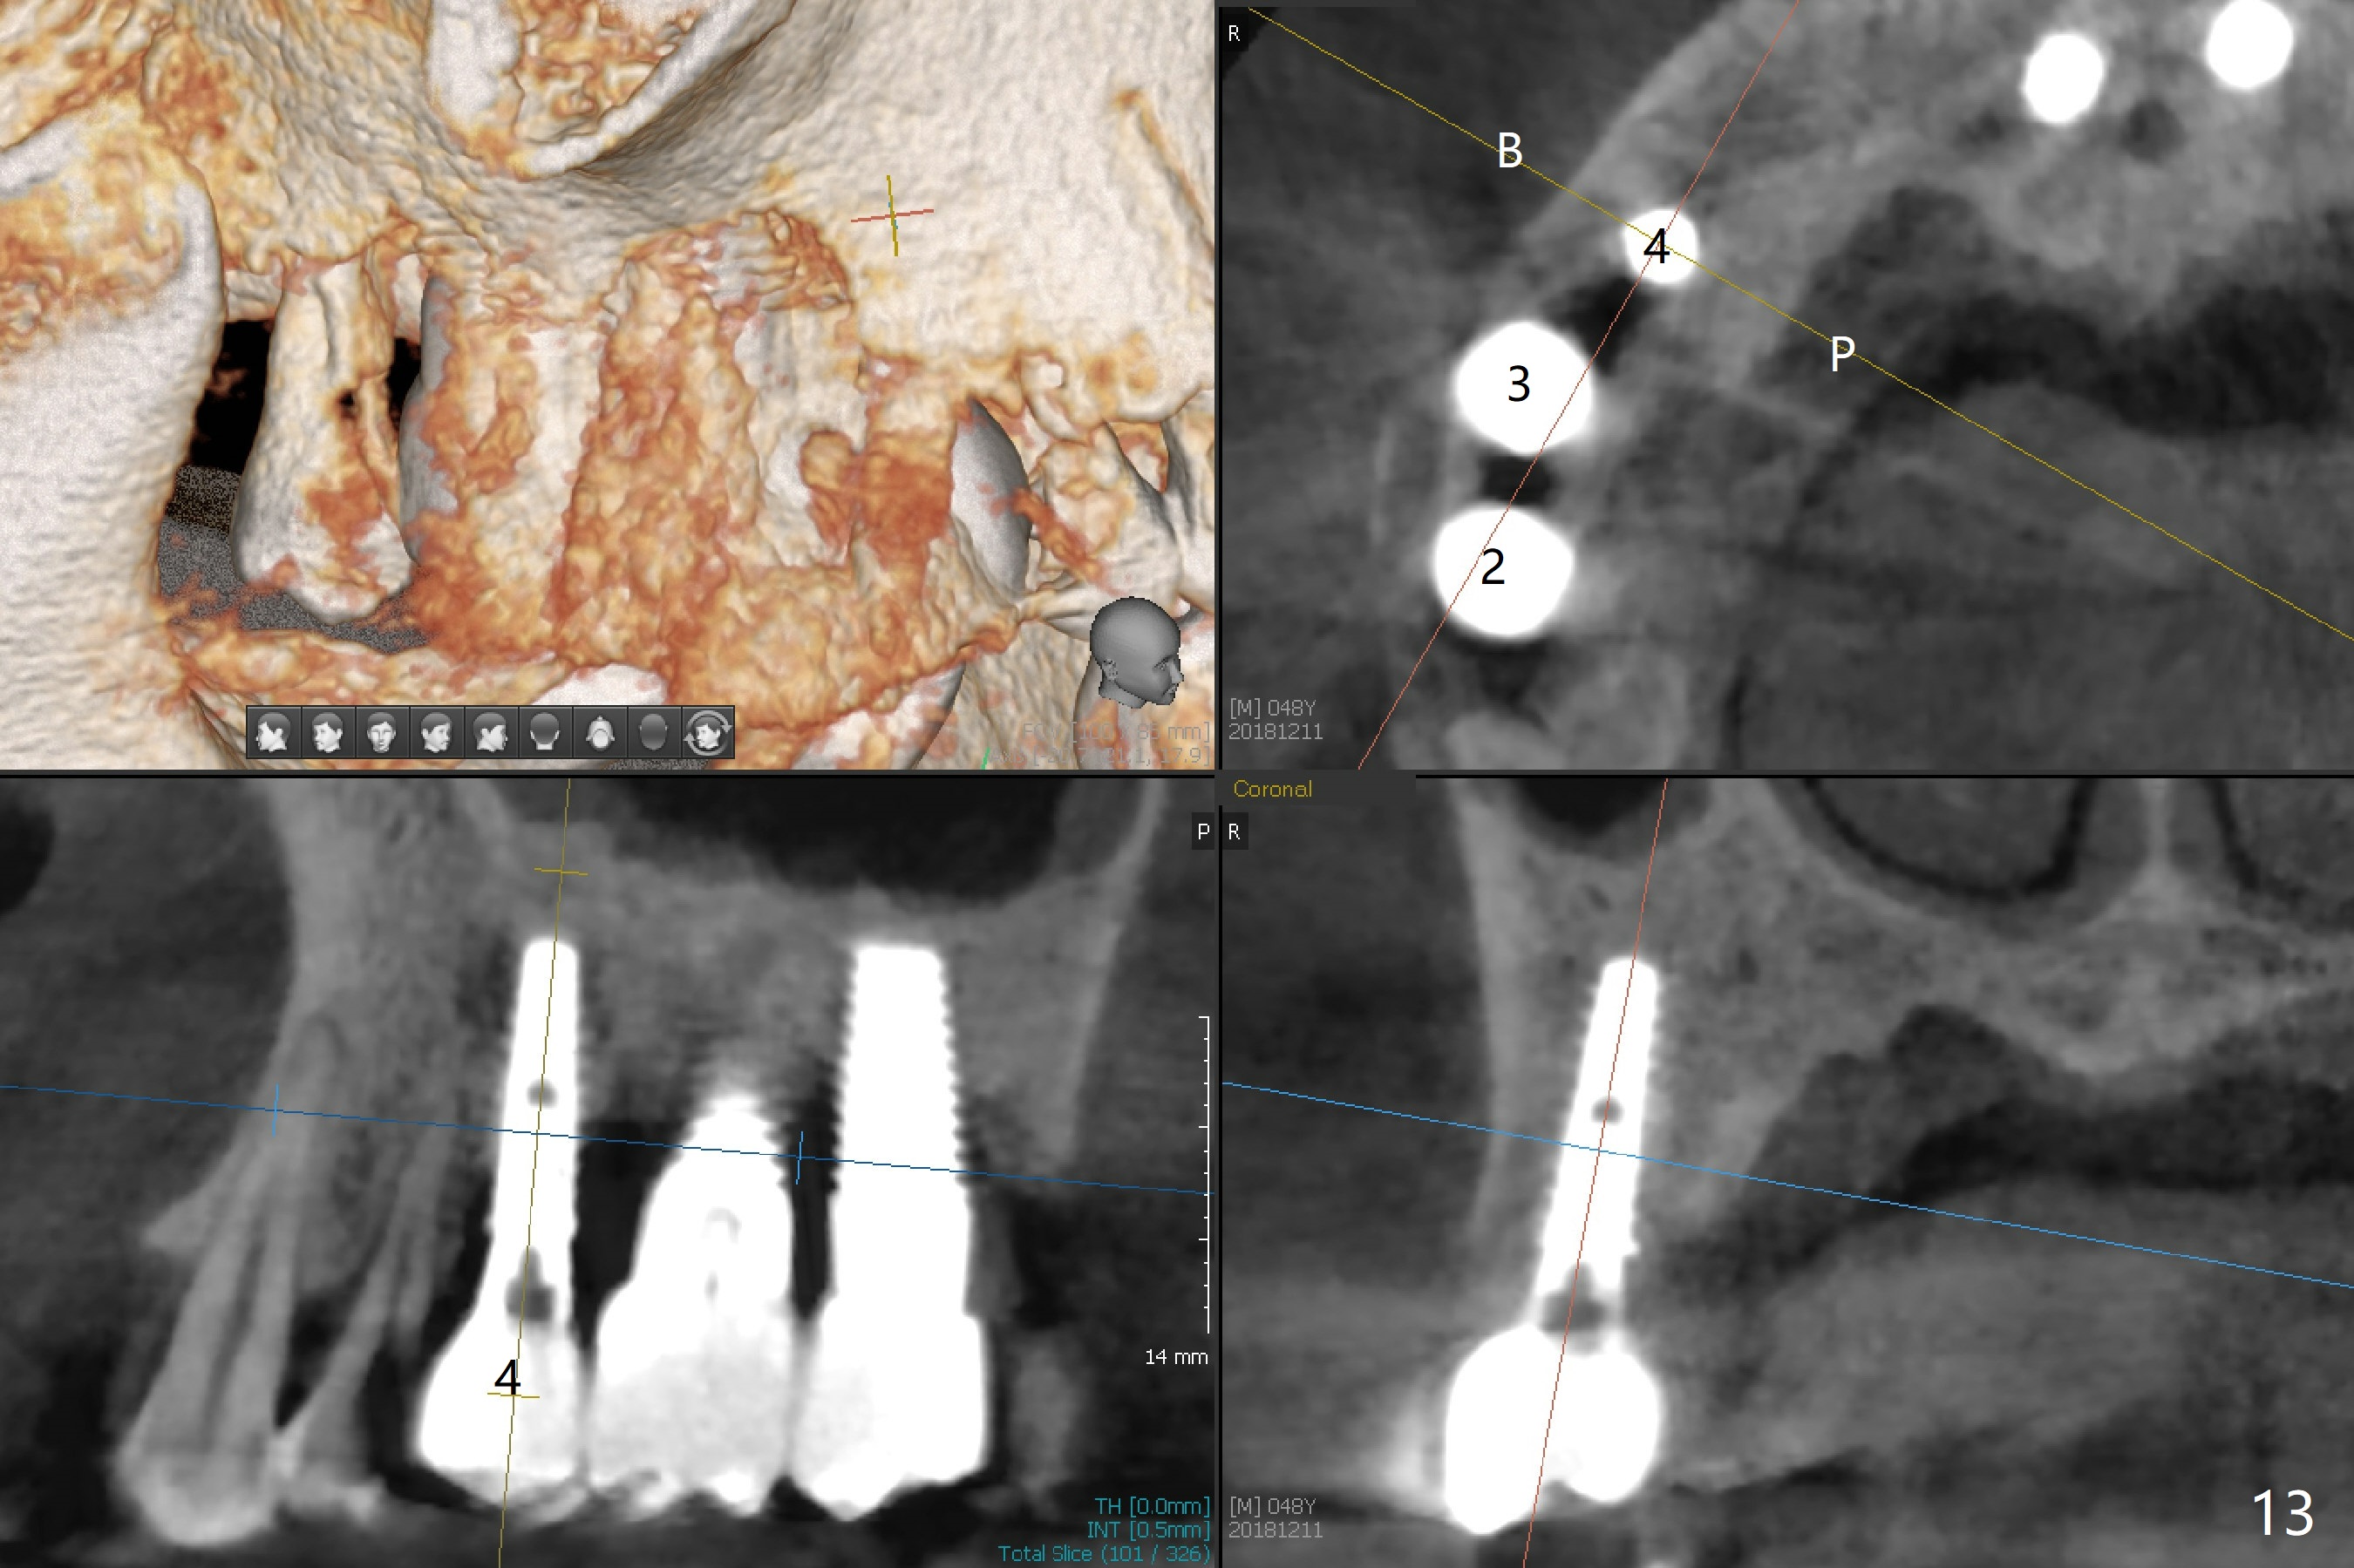

The distal papilla reforms buccally (Fig.8 *) and palatally (Fig.9) 4 months postop.  It appears that the 4 mm cuff of the pair abutment (Fig.10 >) is apical to the mesial crest (*).  The distal coronal implant threads seem to be covered by bone graft (Fig.11 <).  Therefore pair abutments with 5 mm or more cuff are required in cases of the uneven bone.   Implants have to be placed deep.  CT taken 3 months post cementation (10 months postop) shows that the implant is placed in the middle of the alveolus without apparent thread exposure.  CT taken 1 year and 8 months post cementation (Fig.13) shows that the implant is placed in the middle of the alveolus without apparent thread exposure, as compared to those at #2 and 3, which are placed buccal (B).